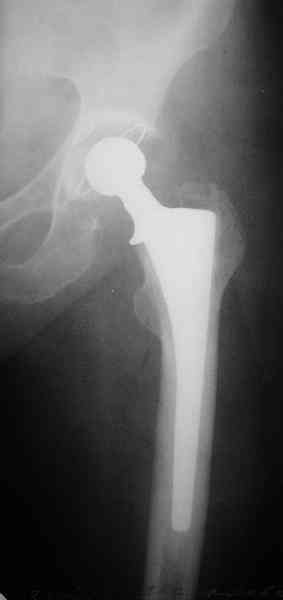

на прошлой неделе прооперировали эту пациентку, рана заживает спокойно, начала ходить с костылями без опоры на поврежденную конечность.

С уважением, Максим Агалаков